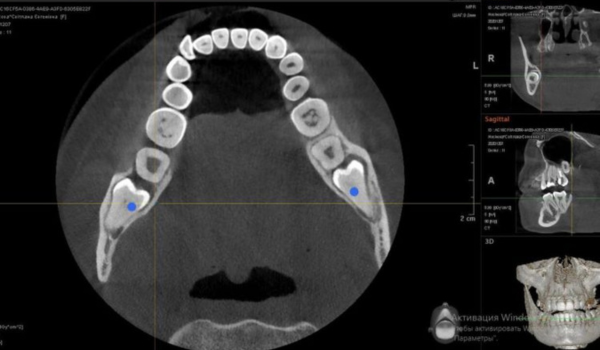

Особливості аналізу КТ зображень в клінічній практиці лікаря хірурга-стоматолога

✔️ Принцип роботи КПКТ, МСКТ, існуючі обмеження, вибір параметрів під кожен клінічний випадок

✔️ Хірургічно значущі анатомічні структури та їх варіабельність за даними КПКТ

✔️ Роль КПКТ у передопераційному плануванні хірургічних втручань

✔️Оцінка якості та морфології кісткової тканини за даними КПКТ